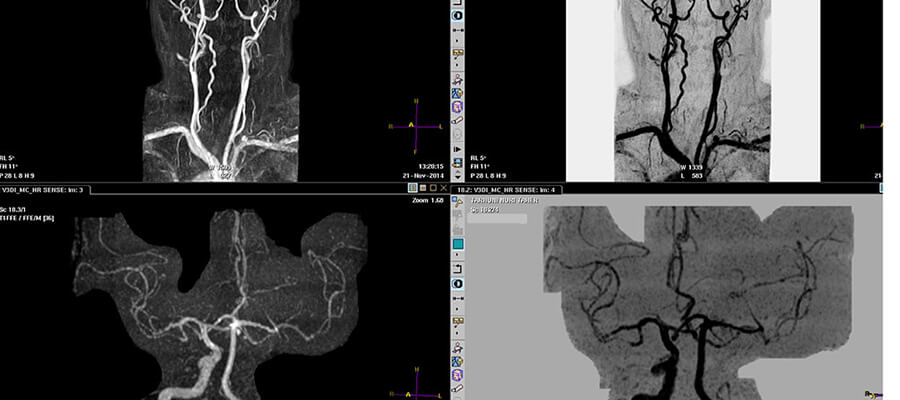

MR Anjiyografi

mr anjiografi

MR Anjiyografi Nasıl Yapılır?

Anjiyografi işlemi kişinin damar ve damarlarda bulunan kan akışının görüntülenmesine yardımcı olan bir tedavi işlemidir. Bu yöntem ile hastada bulunan büyük ana damarların görüntülenme işlemi yapılmaktadır.

MR anjiyografi işleminde bilindiği üzere kişinin damarları ve damarlarında bulunan kan akışının çekimi yapılmaktadır.

MR anjiyografi işlemi kişinin damar ve damarlarında bulunan kanın akışını görüntülemek adına başvurulan tedavilerden biridir. İlaç veya ilaçsız olarak iki şekilde uygulanabilen tedavide kişinin damarlarını ve damar dokularını daha ayrıntılı bir şekilde görmek adına ilaçlı MR anjiyografi işlemi tercih edilmektedir. Bu görüntüleme işlemi yaklaşık otuz beş veya kırk dakika gibi bir sürede ağrısız acısız bir şekilde yapılmaktadır.